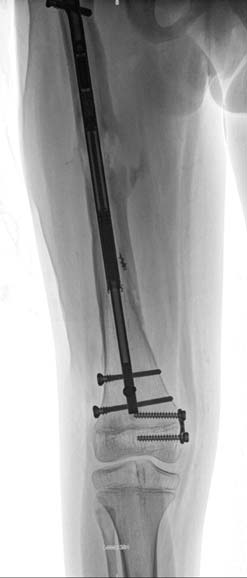

股骨术前前后位和侧位X光片。(B) 使用外固定器辅助,在扩髓前进行截骨术,以矫正既往的刺刀样畸形的髓管对线。(C) 植入PRECICE 1 12.5毫米髓内钉后的前后位和侧位X光片。刺刀样畸形已纠正。(D) 延长5厘米后的前后位和侧位X光片。可见良好骨愈合。患者最终完全愈合。)